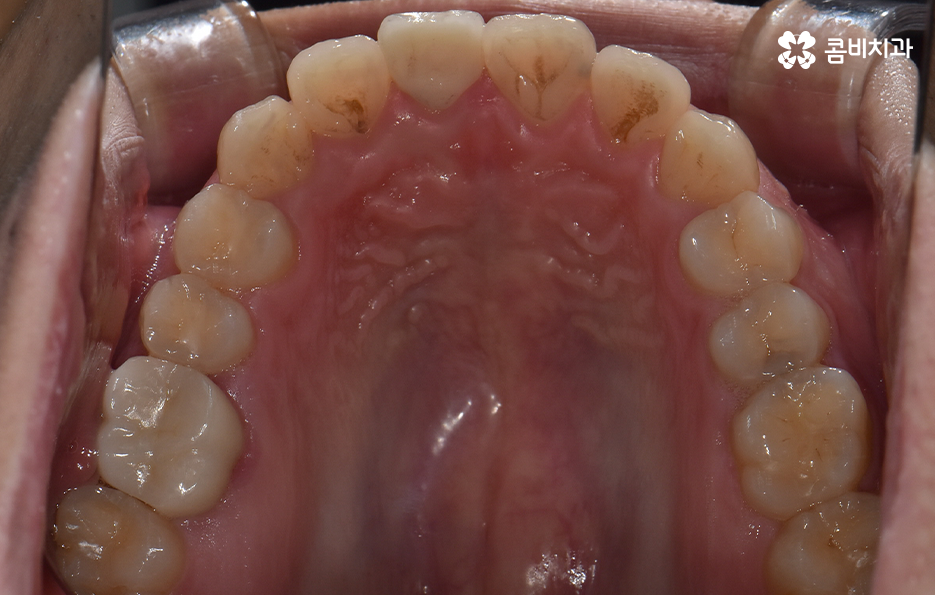

하지만 위에 보시는 환자분의 사례는 윗니와 아랫니의 교합을 고려하고 얼굴형, 골격 등을 고려했을 때도 아랫니만 교정이 가능했던 사례인데 일반적으로 윗니가 아랫니를 살짝 덮고 있어야 하는데 아랫니의 앞니 부분이 유독 안으로 들어와 있었기 때문에 아랫니교정 만으로도 치아교정이 가능했던 사례라고 보시면 좋을 거예요

위 환자분의 사례로 보면 아랫니 중에 하나가 유독 앞으로 튀어나와 있고 나머지 치아는 안으로 들어가 있기 때문에 교합으로 따져볼 때는 아랫니를 전체적으로 앞으로 이동시켜야 했기 때문에 비발치로도 충분히 교정이 가능했고 아랫니교정 만으로도 치료가 가능했어요